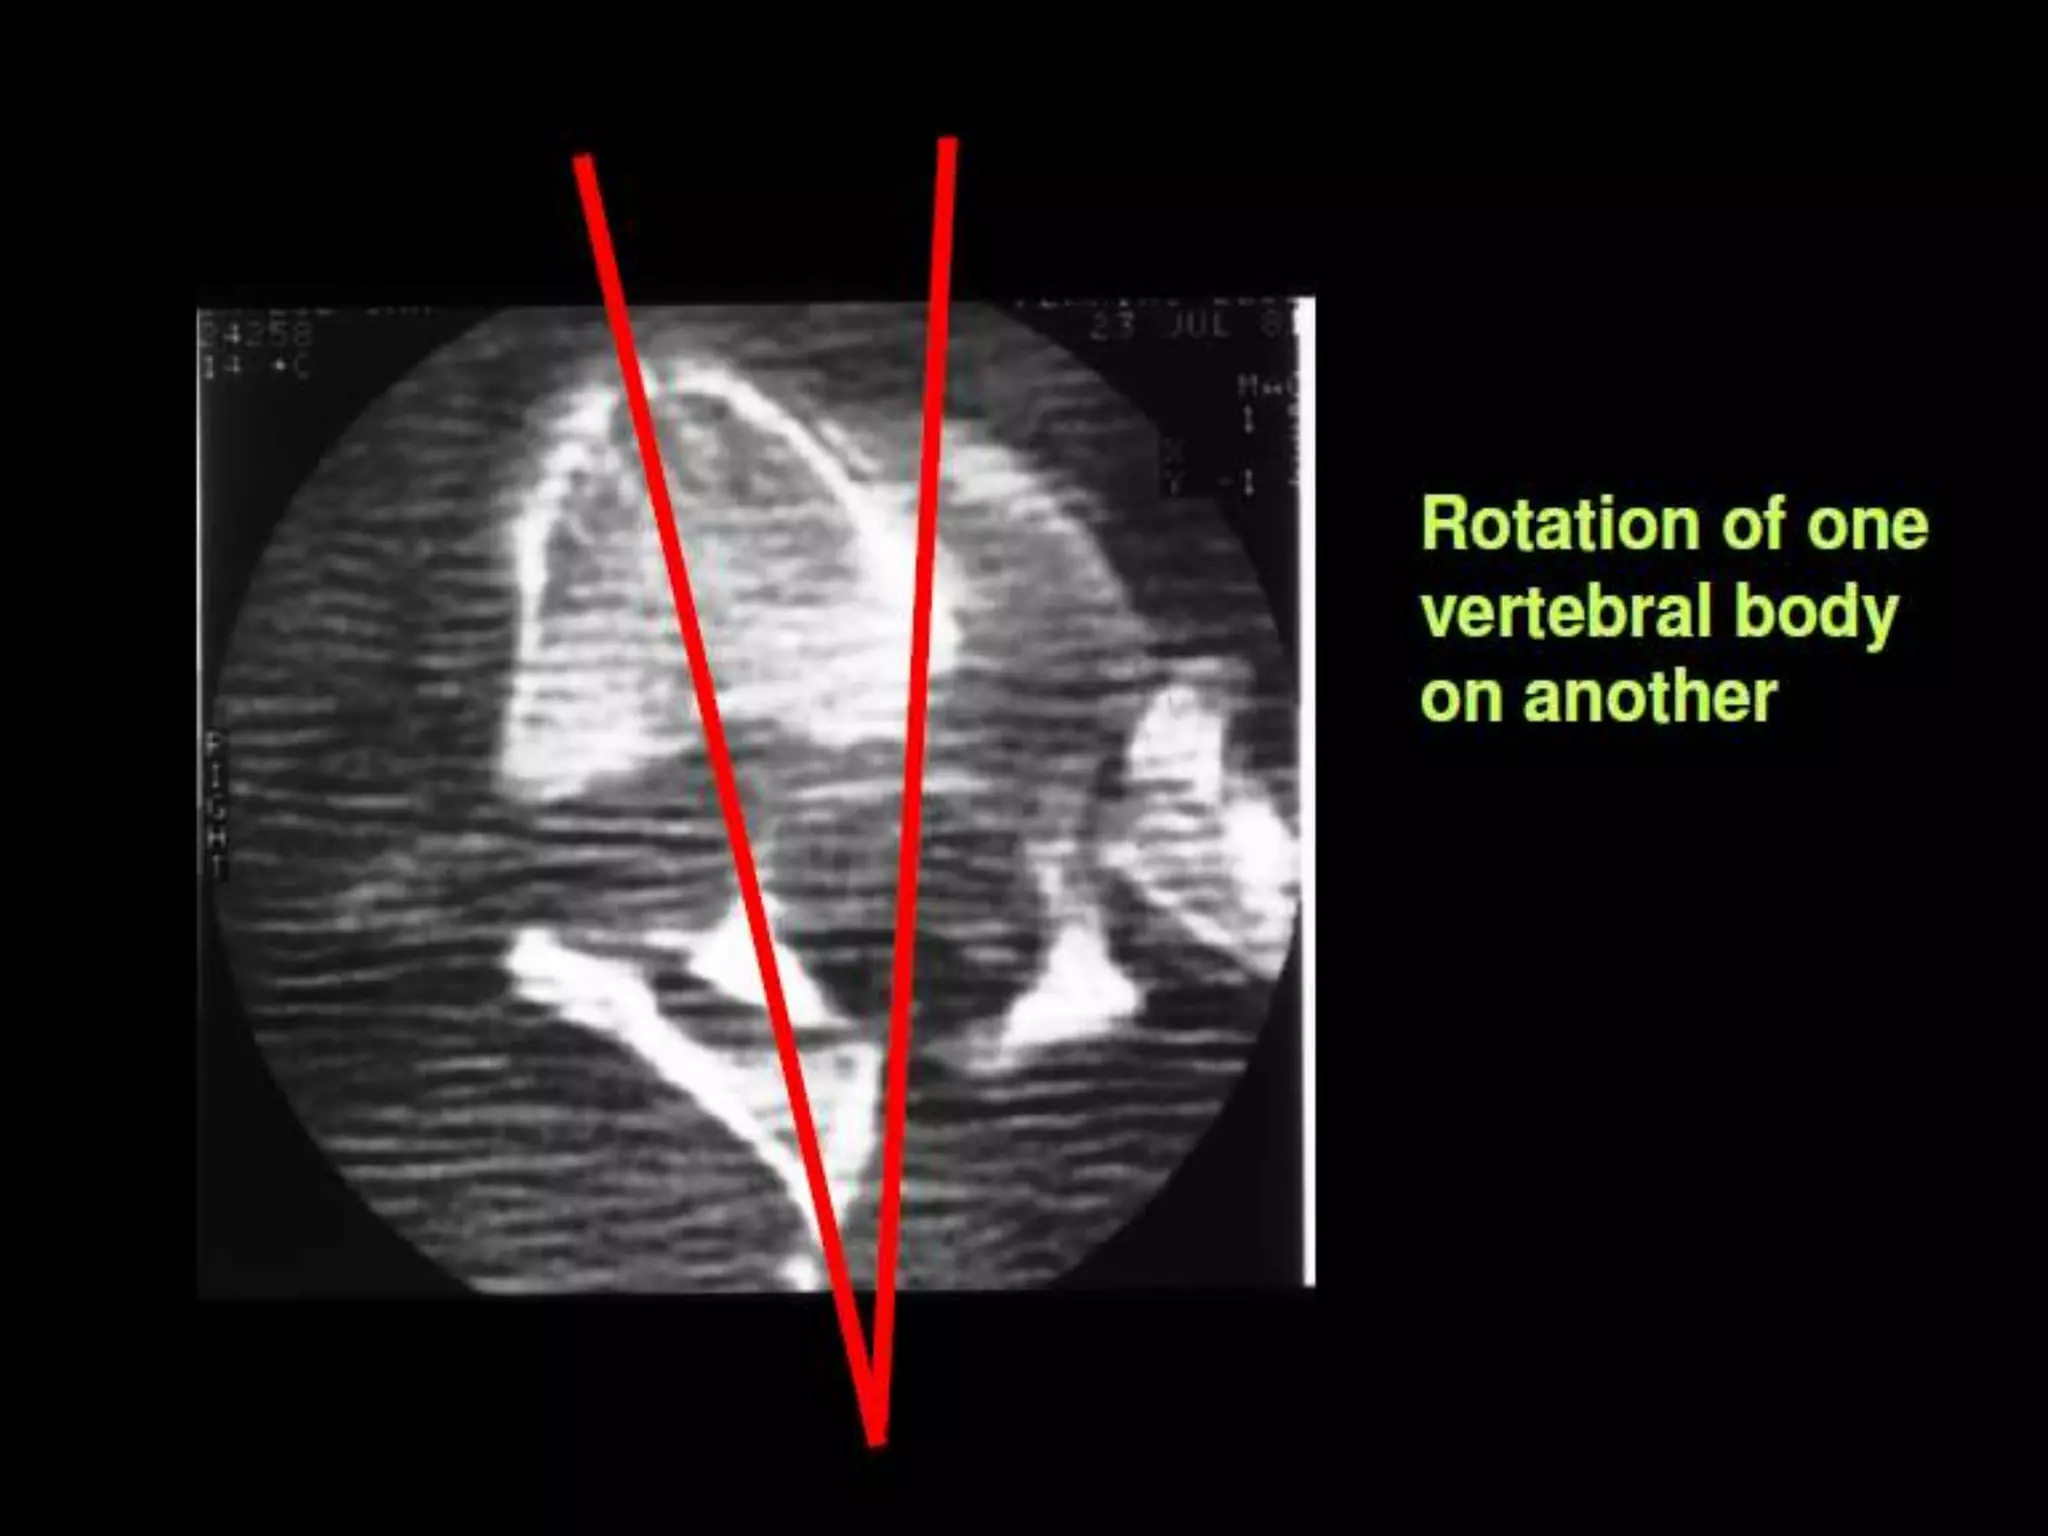

Flexion / Rotation:

• T/L junction.

• Flexion vector: anterior wedge or burst.

• Rotation: addition of this vector tends

to result in instability.

– disruption of posterior ligaments.

– posterior element fracture.

– can lead to dislocation.

• High incidence of neurologic deficit.